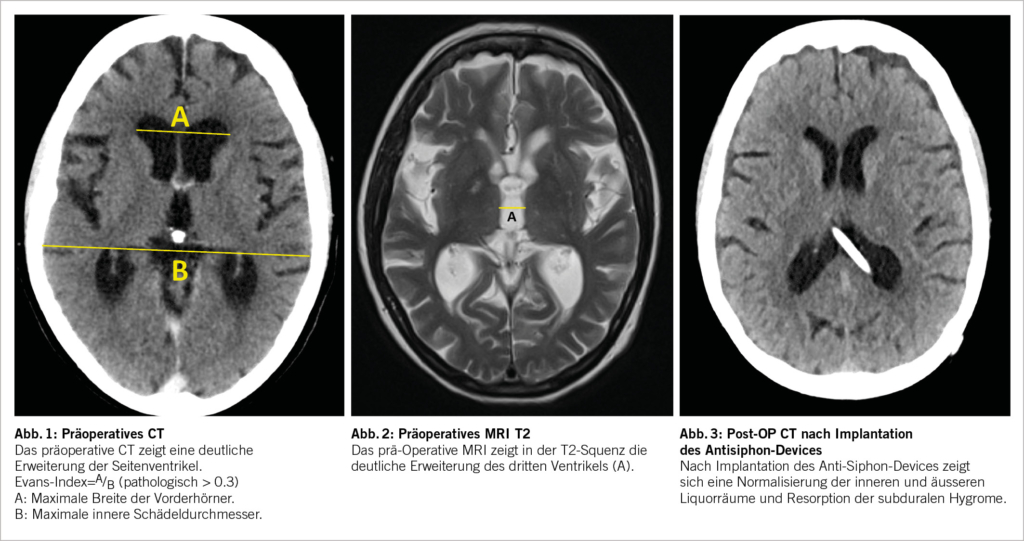

Typischerweise ist beim NPH eine überproportionale Erweiterung der Seitenventrikel mit Ballonierung der Frontalhörner, Temoralhörner und des dritten Ventrikels zu beobachten (Abb. 1-3). Als quantitative Kriterien haben sich einerseits ein erhöhter Evans-Index >0.3 (Verhältnis zwischen maximaler Weite der Vorderhörner und dem maximalen inneren Schädeldurchmesser auf einem axialen Schnittbild, vgl. Abb. 1) sowie der Corpus-callosum-Winkel etabliert (1, 9, 10). Zur genauen Berechnung des Corpus-Callosum-Winkels bedarf es einer 3-D-Rekonstruktion, was aufgrund der Praktikabilität im Alltag eher sekundär ist und idealerweise von radiologischen Kollegen bei der Fragestellung berechnet wird. Dabei wird auf einer koronaren Schicht auf die Commissura posterior zentriert und exakt zur AC-PC Orthogonal-Linie und Fissura longitudinalis cerebri ausgerichtet. Auf dieser Schichtebene wird dann der Winkel zwischen der medialen Wand des Seitenventrikels gemessen (Normalwerte 100-120°, NPH 50-80°, Cut Off 90°). Das Sulcus cinguli-Zeichen ist eine neuere MR-Beschreibung, wobei sich der posteriore Anteil enger als der anteriore darstellt (11).

Bei der ersten postoperativen Kontrolle nach 6 Wochen gab die Patientin zwar eine Besserung der Hakim-Trias an, beklagte jedoch starke positionsabhängige Kopfschmerzen. Das Schädel-CT zeigte typische radiologische Zeichen einer Überdrainage mit sehr schmalen Seitenventrikeln und subduralen Hygromen. Nach Umstellungen des Shunt-Ventil-Druckes auf höhere Drücke verschlechterte sich die Gangataxie weiter und es konnte keine Besserung der positionsabhängigen Überdrainage erreicht werden. Somit wurde die Indikation zur Implantation eines positionsabhängigen Antisiphon-Gravitationsventils gestellt und in Lokalanästhesie infraklavikulär im distalen Shunt-Schlauch zwischengeschaltet. Die Patientin zeigte bereits nach 2-3 Tagen eine komplette Regredienz der Kopfschmerzsymptomatik bei gleichzeitiger Normalisierung des Gangbildes. Nach 6 Wochen hatte die inzwischen klinisch unauffällige Patientin auch im Schädel-CT eine komplette Resorption der subduralen Hygrome sowie eine Normalisierung der inneren Liquorräume. Ein Jahr postoperativ zeigte die Patientin weiterhin einen sehr erfreulichen Verlauf mit völliger Selbstständigkeit im Alltag, wobei weiterhin leichte kognitive Einschränkungen vorhanden waren.